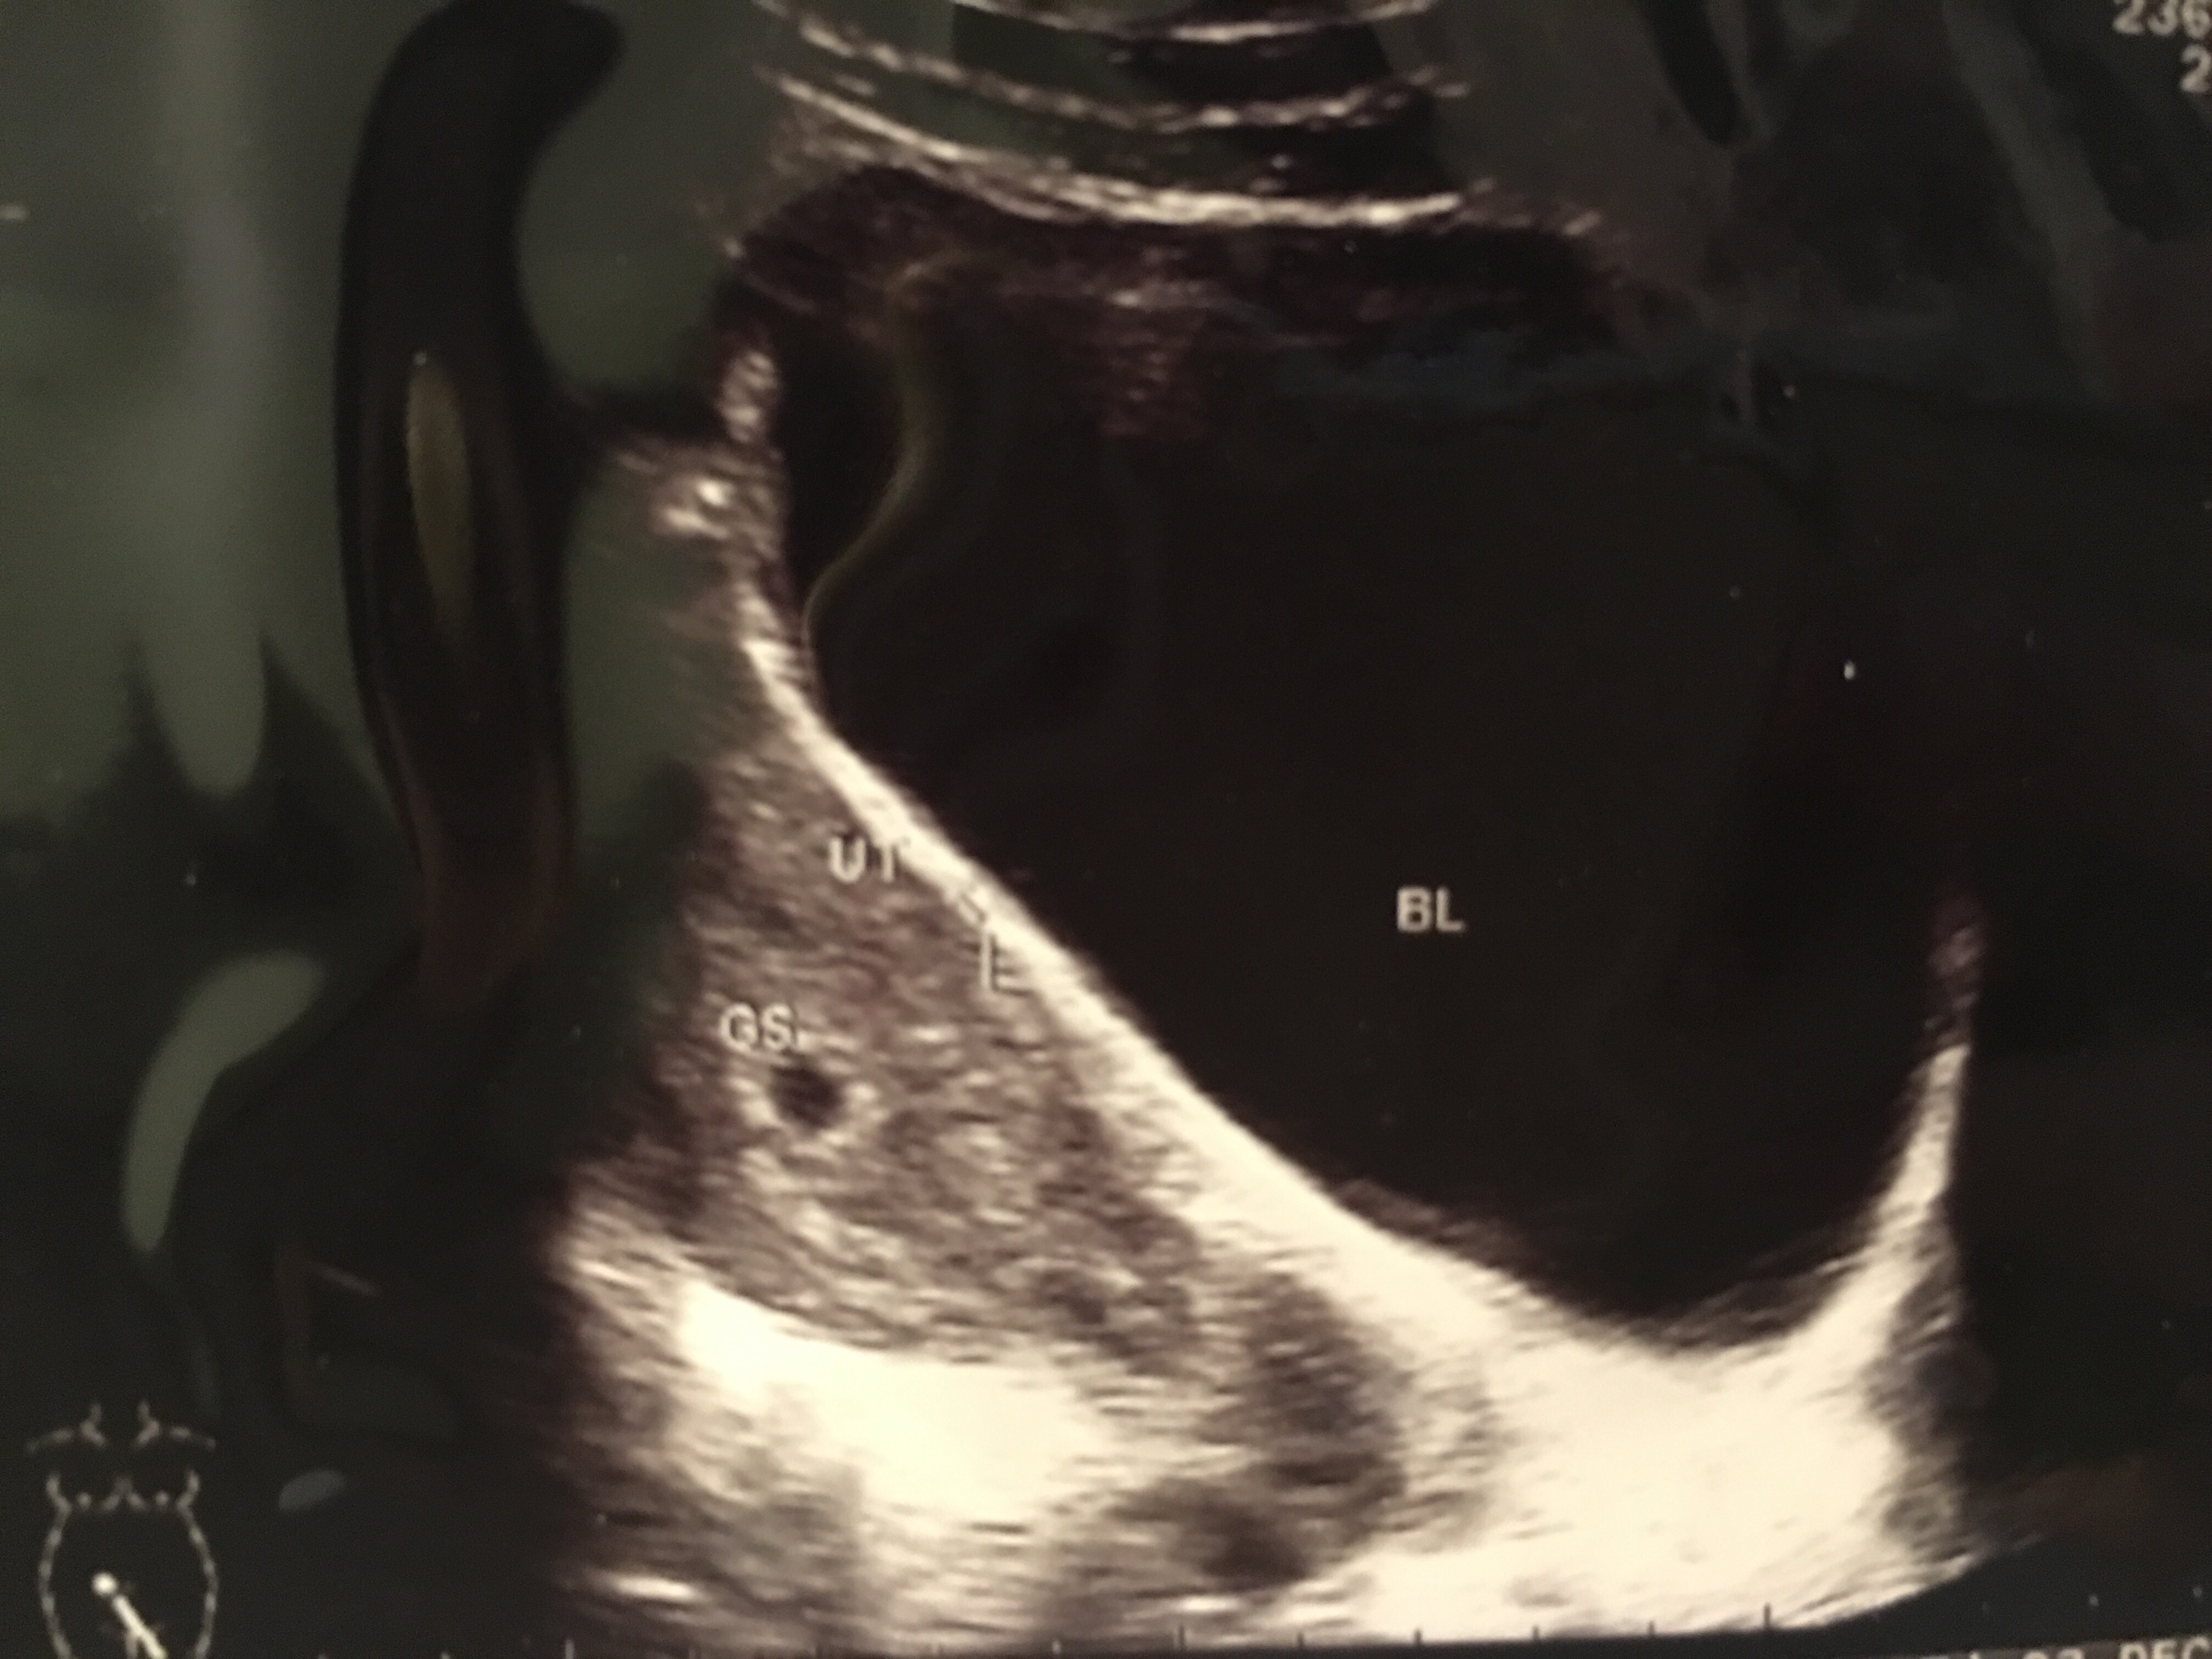

見完診所醫生離開後,腦裡還是一片空白,究竟下一步做什麼?回家將消息告訴家人,讓他們歡喜了一輪。然後想起醫生的話,為何明明真實懷孕,還要照超聲波證實是否真懷孕,真是矛盾。不過還是去找了一間有超聲波的診所看了。BB 6週大了,目前在子宮內,情況正常,懷孕成功。

原來就算驗孕證實了,還要證明是宮外孕,還是宮內孕,宮外孕,就是假懷孕,很快就會流產,只有宮內孕,才會落地生根發展成為BB。沒有讀生物,這些知識真的不懂。

望著超聲波圖,一個黑色的點,這個就是我的孩子,他將來會不斷長大,慢慢由一粒種子大小,變成一個西瓜大小,然後出世。